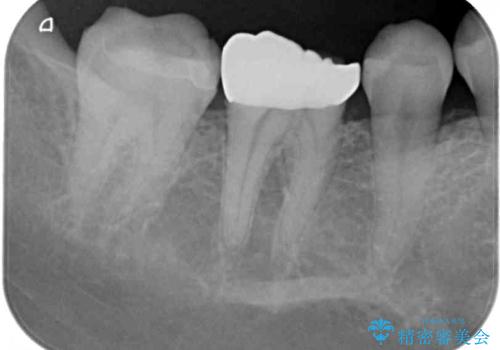

- セラミッククラウンが度々欠けてしまうとのことで来院された患者様です。

セラミッククラウンを装着するには、削る量がやや少ない印象であったので、クラウン破折リスクを回避するために削る量を少し増やすこととしました。

また、咬合力が強いため、強化セラミックのみで製作するフルジルコニアクラウンにて補綴治療することとしました。